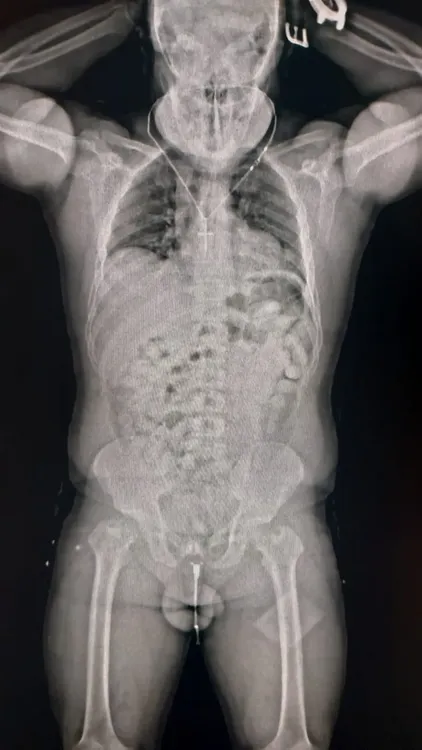

Ante todos los indicios, los guardas inspeccionaron su equipaje, pero no encontraron nada. Dado que las dudas persistían, decidieron utilizar otro método de control: el body scan. Las imágenes confirmaron las sospechas del personal aduanero dado que mostraban cuerpos extraños.

Ante la posibilidad de que se tratase de un método de ocultamiento de estupefacientes, se internó al pasajero en un centro médico y lograron confirmar que había ingerido cápsulas con droga. En total eran 84 y contenían 1134 gramos de cocaína que en el país de destino se podría vender a USD 51 mil.